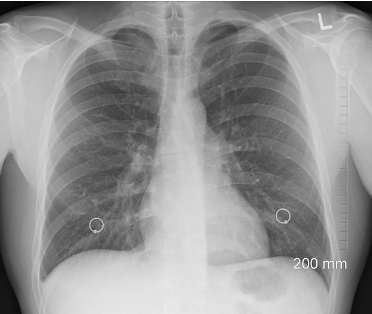

요즘 어른, 아이 할 것 없이 폐렴으로 난리인데요.

가족이 폐렴에 걸렸다면, 폐렴이 뭔지, 전염성이 어느 정도 인지 궁금하실 텐데요.

마이코플라스마 폐렴, 폐렴 전염성, 폐렴에 좋은 음식까지 지금 바로 알아보시기 바랍니다.

마이코플라스마 폐렴은 주로 늦가을인 10월부터~ 초봄 4월까지 유행하며,

마이코플라스마균이 호흡기를 통해 들어와서 발생하는 급성 호흡기 감염증입니다.

마이코플라스마 폐렴은 3~4년 주기로 유행하며, 잠복기는 12~14일 정도입니다..